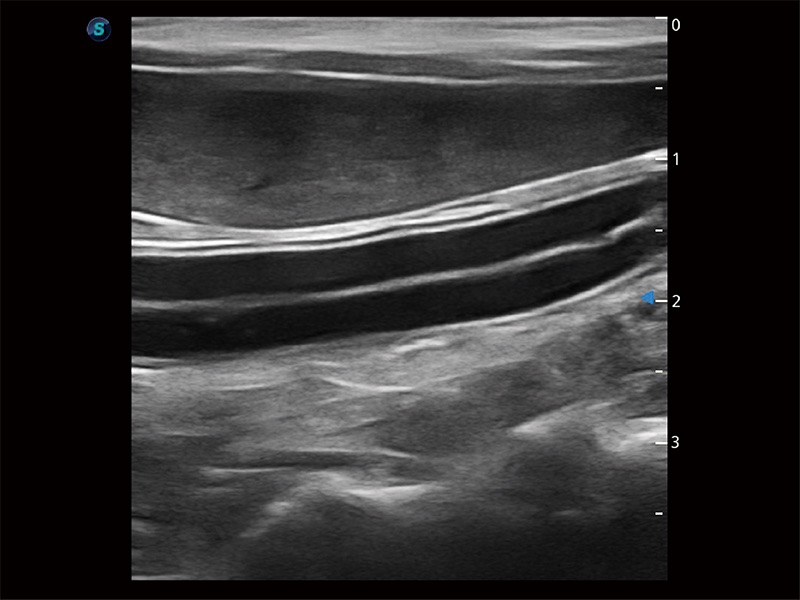

优异的基础图像

ProPet 80 全新的动物超声智能软件和丰富的探头群,为动物医生提供了高清晰度和精细分辨率的图像,无论在宠物、马科、畜牧还是实验室动物等应用中都可以轻松应对,为您的日常工作带来满意的体验。

(猫)二尖瓣M型